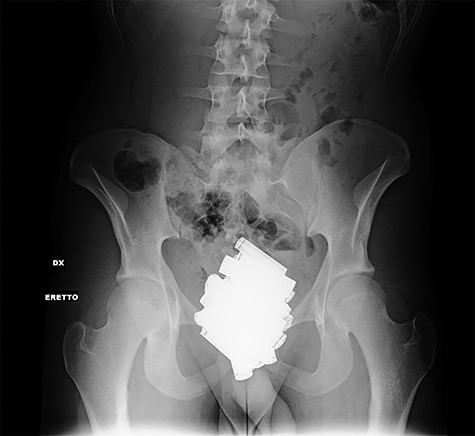

At hospitalization, the clinical examination revealed moderate pain in the lower left part of the abdomen. Laboratory analyses demonstrated moderate neutrophilic leukocytosis. Abdominal X-rays revealed the presence of many radiopaque foreign bodies on the projection of the rectum, referable to stylus batteries (Figs 1 and 2).

Erect abdominal X-rays (frontal view): presence of many radiopaque foreign bodies in the pelvis